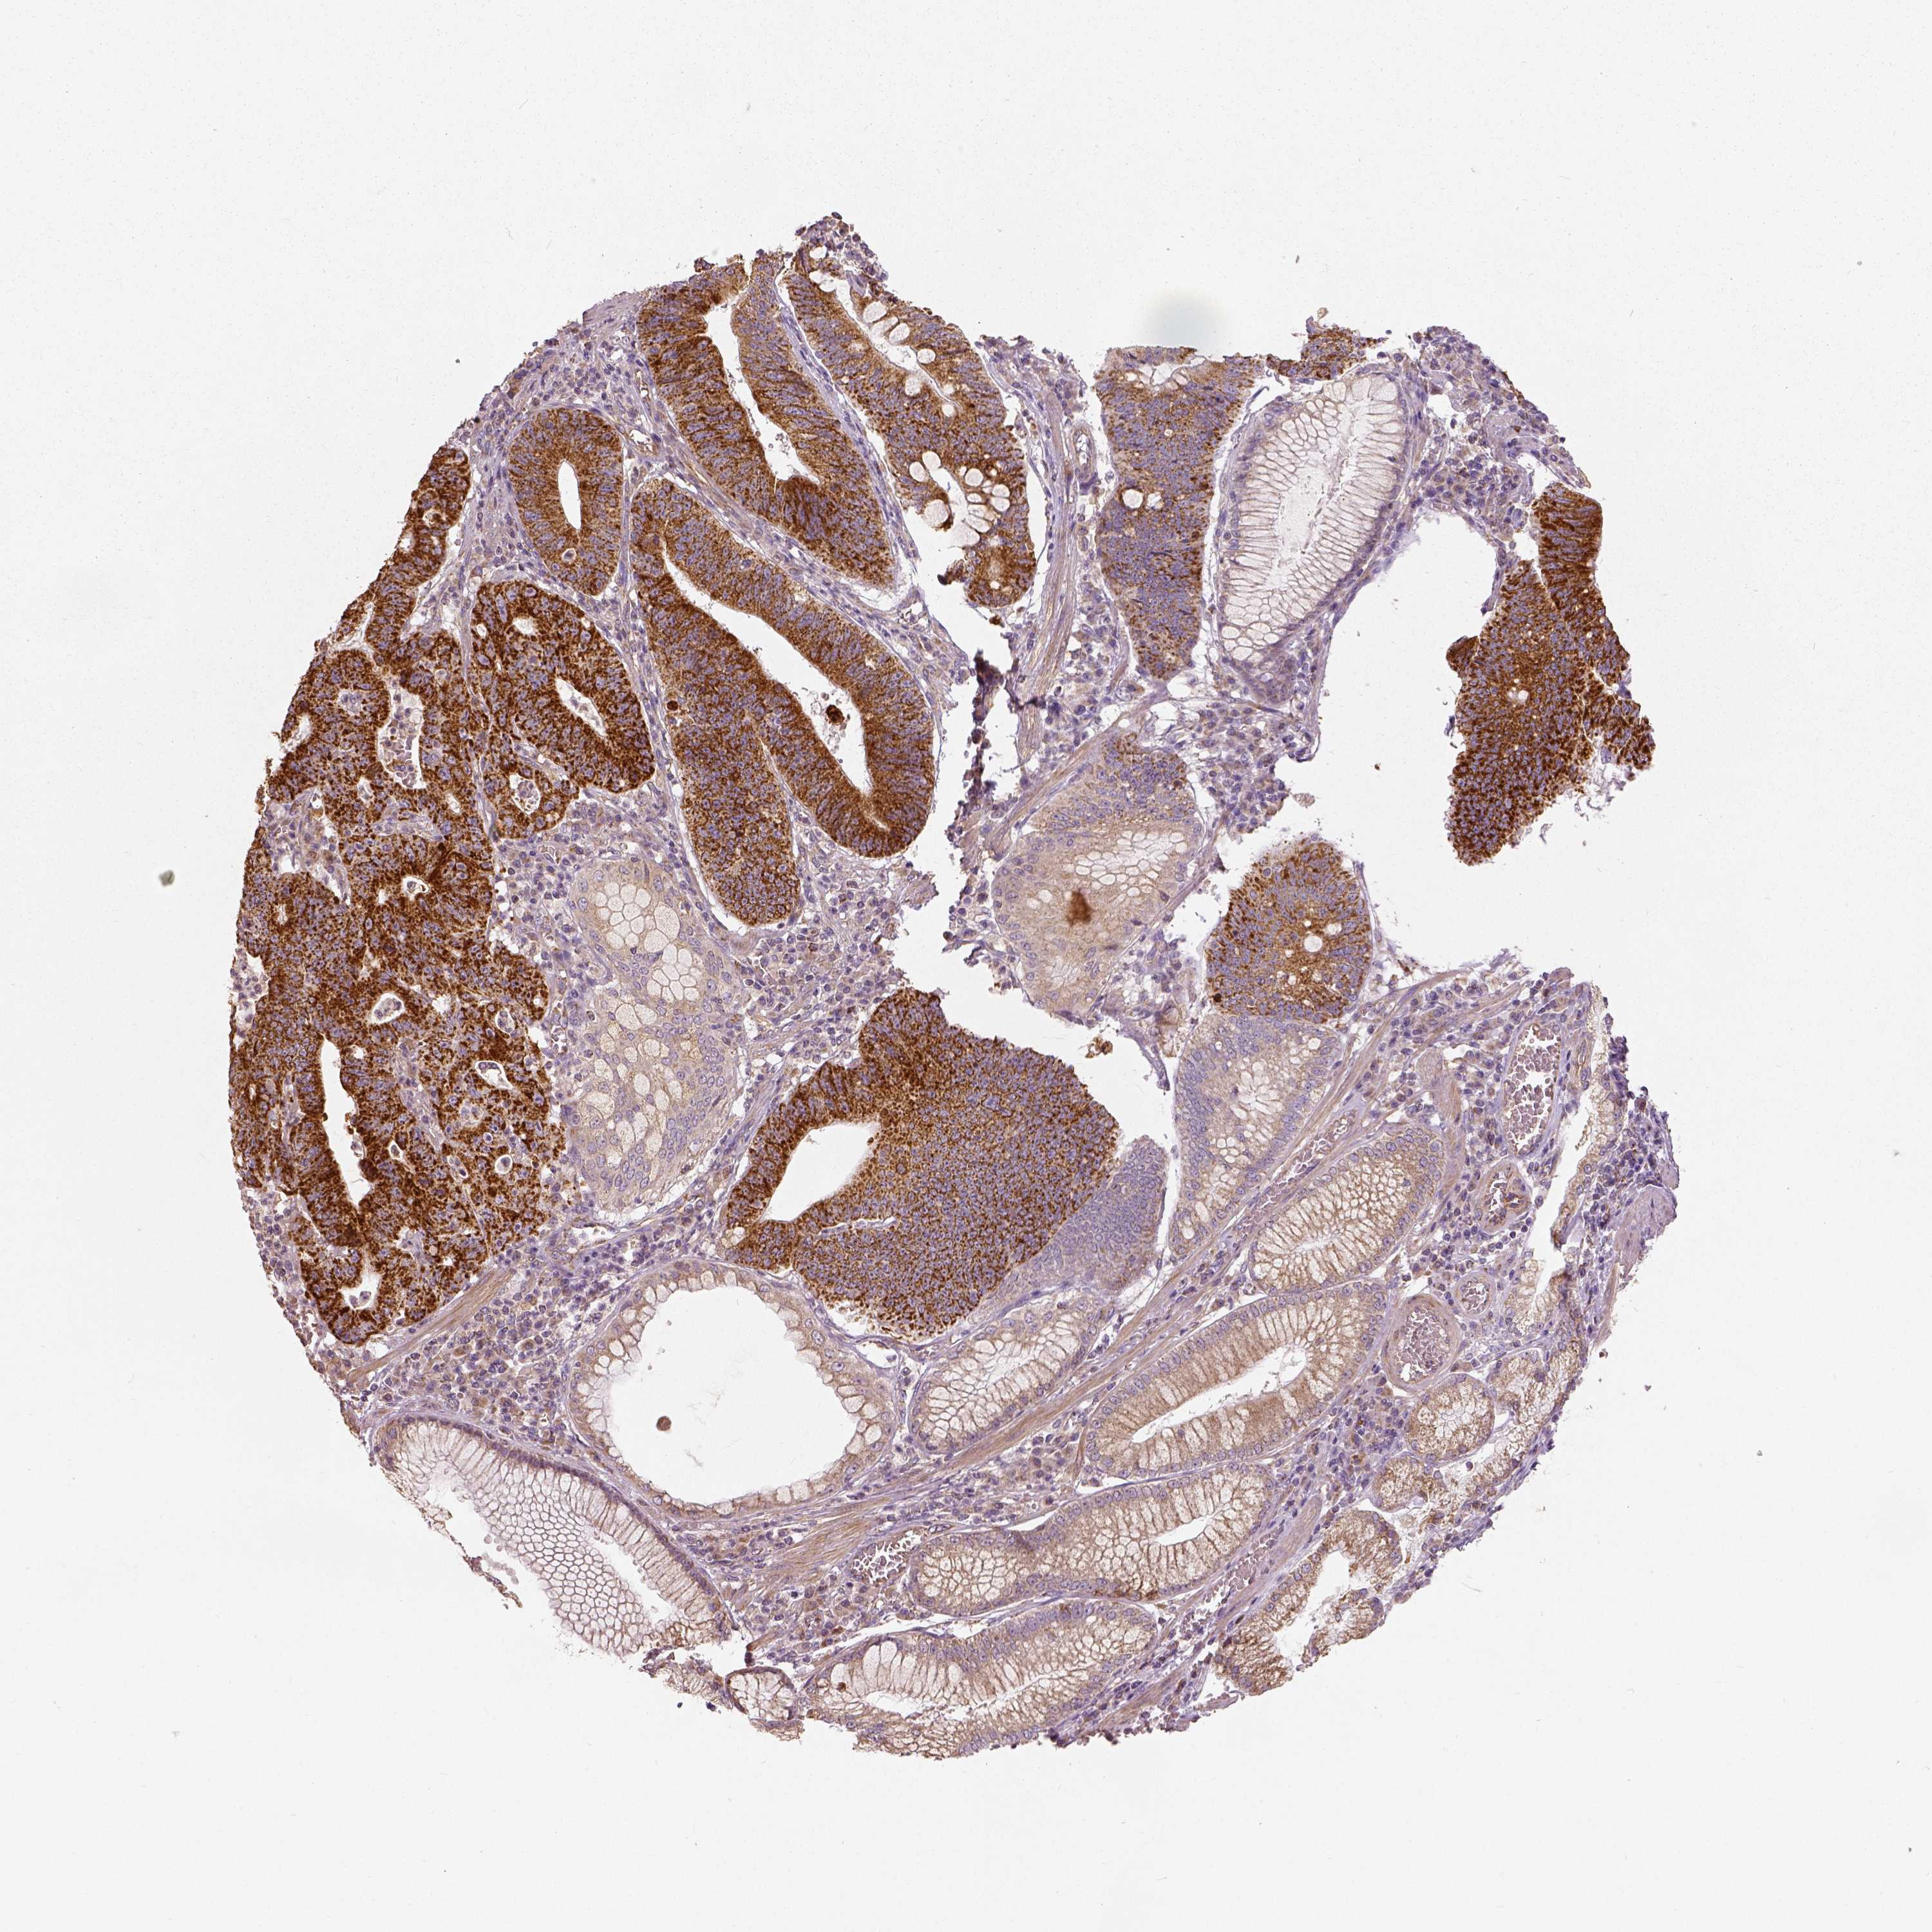

STOMACH CANCER - Protein expressioni

A mouse-over function shows sample information and annotation data. Click on an image to view it in a full screen mode. Samples can be filtered based on level of antibody staining by selecting one or several of the following categories: high, medium, low and not detected. The assay and annotation is described here.

Note that samples used for immunohistochemistry by the Human Protein Atlas do not correspond to samples in the TCGA dataset.

Antibody stainingi

Antibody staining in the annotated cell types in the current human tissue is reported as not detected, low, medium, or high, based on conventional immunohistochemistry profiling in selected tissues. This score is based on the combination of the staining intensity and fraction of stained cells.

Each image is clickable and will lead to virtual microscopy that enables deeper exploration of all samples and also displays staining intensity scores, fraction scores and subcellular localization as well as patient and tissue information for each sample.

Antibody HPA036978

Antibody HPA036979

Antibody CAB068215

Staining

High

Medium

Low

Not detected

Intensity

Strong

Moderate

Weak

Negative

Quantity

>75%

75%-25%

<25%

None

Location

Nuclear

Cytoplasmic/membranous

Cytoplasmic/membranous,nuclear

Adenocarcinoma, NOS